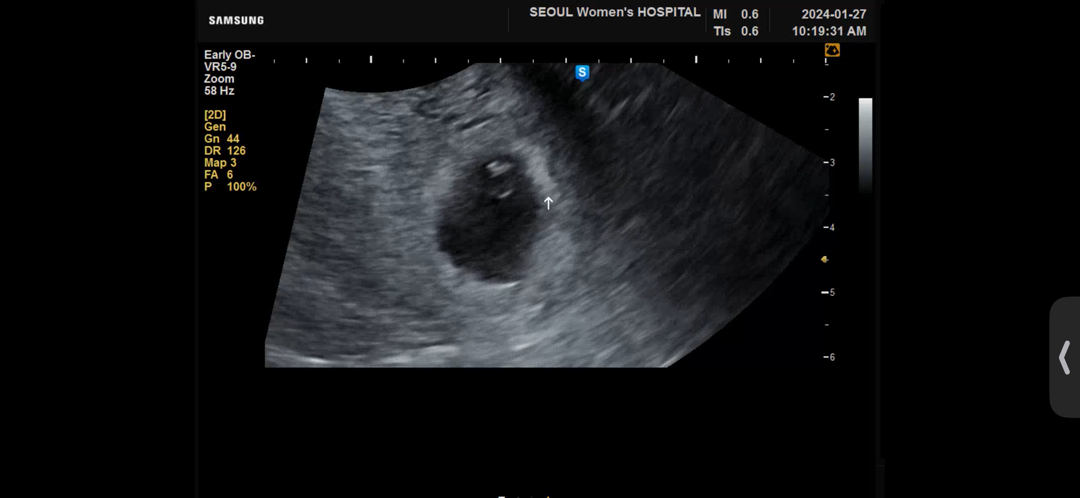

막생 12월16일 1월17일에 아기집에 난황생길랑말랑하는 상태확인하고, 2주뒤에 오라고하셨지만 급한마음에 오늘가서 심장소리듣고왔네요!ㅎㅎ

116bpm이요!ㅎㅎ

오늘 딱 6주0일차요!